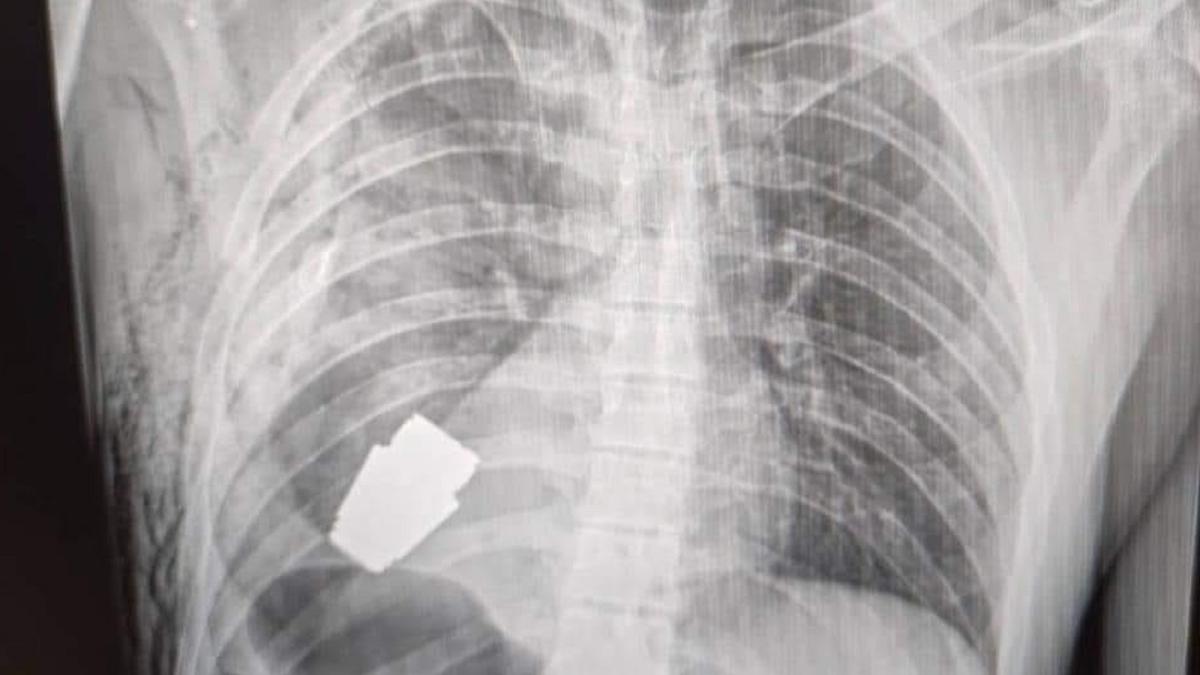

Un soldat a supraviețuit recent la limită după ce a primit o grenadă activă înfiptă în piept și a avut nevoie de o intervenție chirurgicală pentru a îndepărta bomba, deși aceasta ar fi putut exploda în orice moment.

Arma în cauză este cunoscută sub numele de grenadă VOG, un proiectil exploziv conceput pentru a fi tras dintr-un lansator de grenade.

Această bombă specială a rămas în trunchiul unui soldat ucrainean, care a fost trimis în continuare la reabilitare și recuperare după o operație reușită.

El a fost nevoit să efectueze procedura chirurgicală fără a utiliza electrocoagularea, care constă în folosirea unui curent electric pentru a distruge țesuturile anormale și a controla sângerarea, de teamă că ar putea detona grenada.